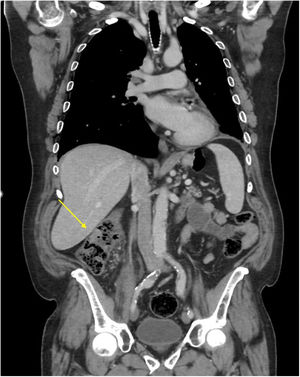

A follow-up CT scan 10 months after diagnosis showed mural thickening of the ascending colon (Fig. 1). A colonoscopy was performed and a superficial ulcer of non-specific appearance was observed in the right colon (Fig. 2). Histopathology was consistent with colonic metastasis of lung squamous cell carcinoma (Fig. 3).